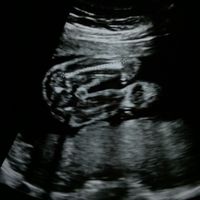

Premetto che sto parlando di un'amica e sono DAVVERO molto felice per lei.Credo che questo sia uno dei tanti esempi di come ogni gravidanza sia seriamente un mondo a parte.Lei è stata a casa da subito...

Buongiorno a tutte ragazze, mi presento, sono Valeria e ho scoperto di aspettare il mio gioiello da appena una settimana. .. come sintomo ho solo seno gonfio e dolori da ciclo... se vi va possiamo...